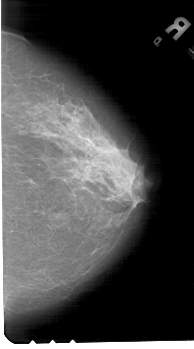

A_1444_1.LEFT_CC

LEFT_CC LINES 5176 PIXELS_PER_LINE 3061 BITS_PER_PIXEL 12 RESOLUTION 43.5 OVERLAY